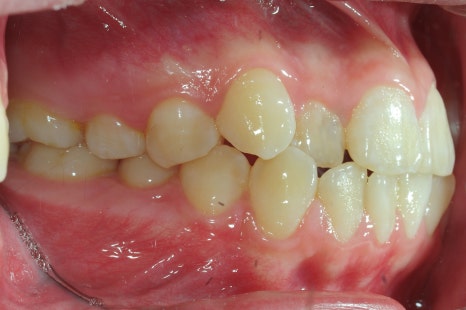

< 스마일디 치과 비발치 before & after >

*치료 전후 사진은 환자의 동의하에 게재하였으며, 동일한 환경과 조건에서 촬영된 전후 사진입니다.

발치 vs 비발치, 무엇이 결정하나요?

교정에서 발치를 하는 이유는 단 하나, 공간 부족 때문입니다.

삐뚤어진 치아들이 가지런히 설 자리가 부족하기에, 치아를 뽑아 그 공간을 활용하는 것이죠.